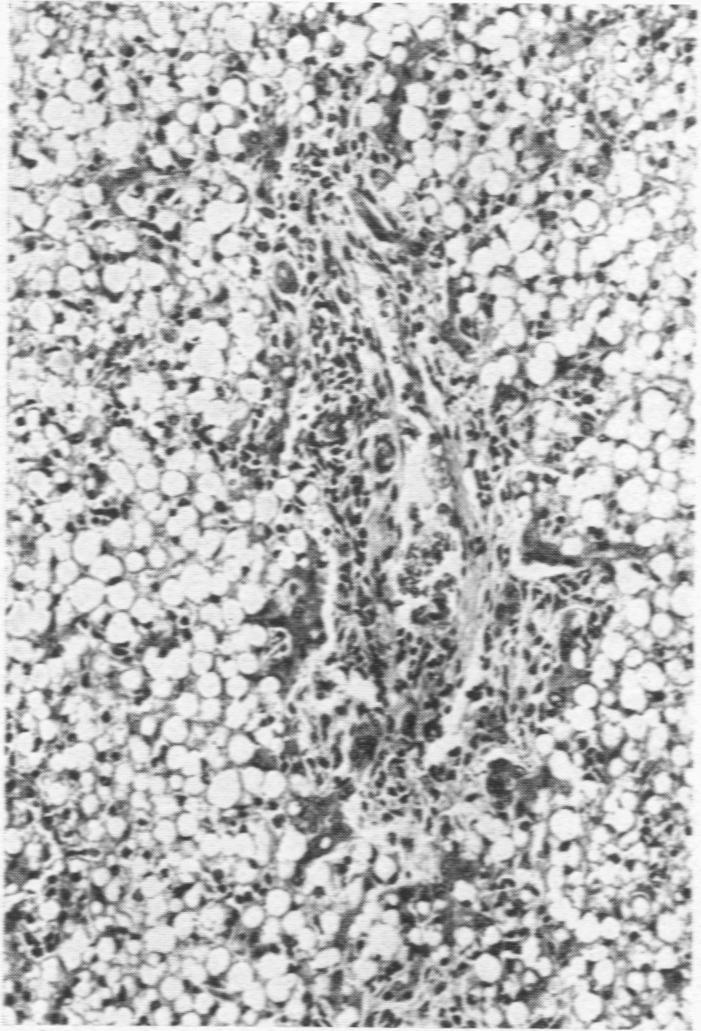

Duodenal ulcers with extensive liver damage in infant twins.

https://cdn.ncbi.nlm.nih.gov/pmc/blobs/a717/1988683/8a47ba7dc10d/archdisch01411-0052-a.jpg